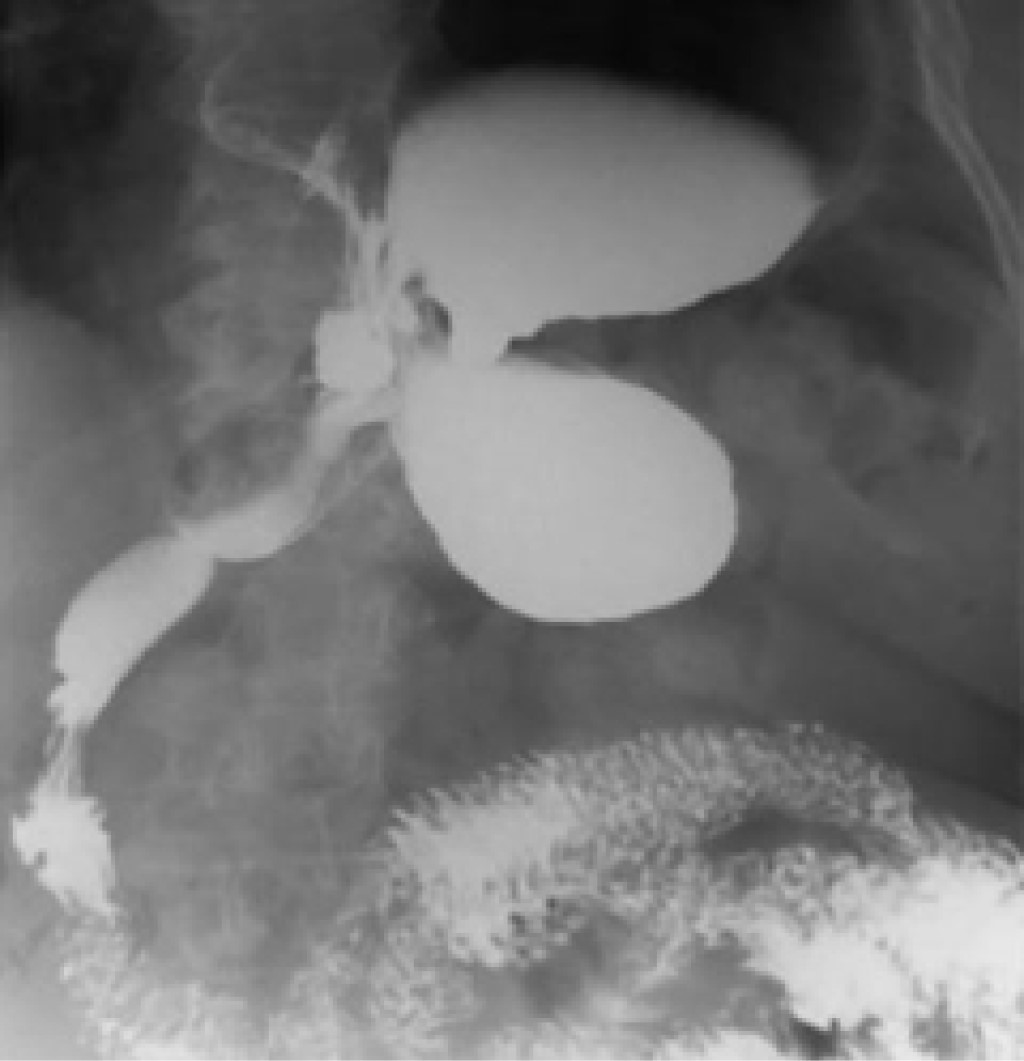

Its clinical presentation varies according to etiology, speed of progression, type of volvulus, degree of rotation and resulting obstruction, so the symptoms may mimic any abdominal condition. In the acute form, Borchardt's triad (severe epigastric distention with abdominal pain, intractable retching, and inability to pass a gastric tube) is diagnostic in 70% of adult patients.3,10 The subacute form of gastric volvulus is characterized by vague abdominal discomfort, while in chronic GV the symptomatology is nonspecific with epigastric pain, early satiety, nausea or vomiting.8 Other symptoms may be atypical chest pain, anemia, weight loss, dyspnea, reflux, postprandial abdominal distention. or dysphagia and may appear irregularly over weeks or years.7 The high probability of exacerbation of chronic VG should be reminded. Secondary complications of acute GV are gastric ileus, pyloric ischemia, gastric necrosis with perforation, and even death.3,11 Diagnosis is usually difficult due to a low clinical suspicion and can range from being an incidental radiological finding to an urgent situation.12 Abdominal plain X-rays usually show gastric dilatation with gas scarcity in the remaining part of the intestine.2 If the GV is secondary to a diaphragmatic defect, a retrocardiac air bubble or air level may be found in the chest (Figure 3); especially in the mesenteric-axial form the gastric shadow shows a double level of air and fluid in the standing position, while in the organ-axial form, the stomach is more horizontally positioned with a single fluid level.13 An upper gastrointestinal barium series is considered more specific than the plain radiographs, as it reveals the obstruction of the stomach at the site of the volvulus and its distension at the level of the diaphragm (Figure 4).8 In our case, the presentation was not the classic one, and therefore an accurate preoperative diagnosis was not achieved. It was necessary to perform a CT scan, which is consistent with the study by Mazaheri et al, which supports its use since this imaging study has the highest sensitivity and specificity for the diagnosis of GV and an accuracy of 90%. In the CT scan imaging, the most important finding is the transition point of the pyloric peak,14 which confirms the diagnosis with anatomical details and possible associated conditions (paraesophageal and diaphragmatic hernias, diaphragmatic eventration). In a late stage of a GV, the vascular involvement may result in findings of gastric ischemia, ulceration, or gastric mucosal fissures.11,15 The hemodynamic status of our patient did not allow further studies to be performed so we proceeded to perform an urgent exploratory laparotomy. Treatment can be conservative or surgical depending on the clinical presentation and possible associated anomalies. While in the acute phase the GV should be treated with an emergency surgical intervention, there are no clear guidelines on the management of chronic GV.11,14 Initial management should be with a gastric tube placement for decompression, followed by surgery to check gastric viability, resection if necrosis is present, and a definitive surgical treatment such as reduction of rotation, gastrostomy, gastropexy, and repair of predisposing defects.17 In a retrospective study of patients with GV and conservative management for five years, it was found that symptomatic recurrence was 64%, but this is only an option for patients with chronic GV, especially those over 60 years of age and with high surgical risk17 and involves reduction or percutaneous endoscopic gastrostomy plus prokinetic and antisecretory treatment. However, there is a high risk of gastric perforation.16 In our case it was determined that the patient was not a candidate for this type of management.1,18 Minimally invasive surgery, such as endoscopic de-rotation and single incision laparoscopic surgery, has gained ground over classic techniques due to the lower rate of complications, with less bleeding and shorter hospital stay, so it is necessary to establish a standard procedure under this technique. The option of a more drastic management with the performance of a total gastrectomy with end-to-end esophageal-jejunal anastomosis should be considered from the beginning, trying to avoid complications, the risk of infection and repetitive surgical trauma.12

Figure 4